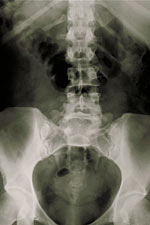

Radiografías de la columna vertebral, del cuello o de la espalda

En las radiografías, se usan haces de energía para generar imágenes de los tejidos, los huesos y los órganos en una placa o una computadora. Las radiografías habituales se hacen por muchos motivos. Entre ellos, el diagnóstico de tumores, lesiones óseas y otras causas de dolor en la columna vertebral.

Los rayos X atraviesan los tejidos del cuerpo para llegar a placas especiales parecidas a películas de cámaras fotográficas. Esto genera una imagen en “negativo”. Cuanto más sólida la estructura, más blanca se ve en la placa. Hoy en día, en vez de usar una película, las radiografías se hacen utilizando computadoras y medios digitales.

Cuando los rayos X atraviesan el cuerpo, las distintas partes del cuerpo permiten el paso de distintas cantidades de haces de rayos. En las imágenes aparecen algunas partes más claras y otras, más oscuras. Cuán claras u oscuras sean esas áreas depende de la cantidad de rayos X que hayan atravesado los tejidos. Los tejidos blandos del cuerpo (como la sangre, la piel, la grasa y los músculos) permiten el paso de la mayoría de los rayos X. Esas áreas se ven gris oscuro en la película. Los huesos o los tumores son más densos que el tejido blando y no permiten el paso de muchos rayos X, por lo que se ven blancos en la radiografía. Cuando un hueso está roto, es decir, hay una fractura, el haz de rayos X pasa a través del área quebrada y se la ve como una línea oscura en el hueso blanco.

Pueden hacerse radiografías de la columna vertebral para observar sus distintas zonas. Llamamos a estas zonas secciones cervical, torácica, lumbar, sacra y coccígea. Para diagnosticar problemas en la columna vertebral, la espalda o el cuello, también pueden realizarse otras pruebas. Estas pruebas son las siguientes: mielografía, tomografía computarizada, resonancia magnética y gammagrafía ósea.